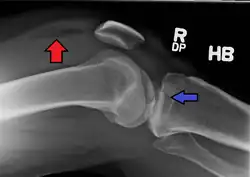

Lipohemarthrosis (presence of fat and blood from bone marrow in the joint space after an intraarticular fracture) seen on X-ray in a person with a subtle tibial plateau fracture

Lipohemarthrosis due to a tibial plateau fracture

A tibial plateau fracture seen on X-ray